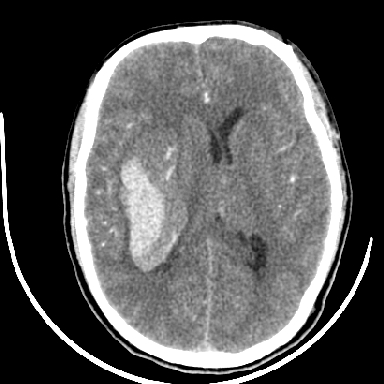

标题: CT6056:脑出血(血管畸形?) [打印本页]

标题: CT6056:脑出血(血管畸形?)

m 40突发头痛左侧偏瘫3小时

考虑高血压性脑出血,依据:

1是高血压性脑出血的好发部位,形态呈肾形,是高血压性脑出血的常见形状

2增强时占位效应加重了,考虑出血还没有停止

3病灶周围水肿不是太厉害,一般肿瘤出血水肿多非常明显

4病灶周围的‘软组织’影没有明显的强化

5至于脑血管畸形引起的出血,暂时没有看到明显的畸形血管影,也不太支持

支持右侧基底节脑出血

右侧基底节区脑出血.

支持右侧基底节区(主要为外囊区)原发性脑出血。

另附部分资料:“血液溢出血管外形成血肿,其内含有大量血红蛋白、血浆白蛋白,球蛋白,因这些蛋白对x线的吸收系数高于脑质,故ct呈现高密度阴影,ct值达40~90h,最初高密度灶呈非均匀一致性,中心密度更高,新鲜出血灶边缘不清。基底节区血肿多为“肾”型,内侧凹陷,外侧膨隆,因外侧裂阻力较小,故向外凸,其它部位血肿多呈尖圆形或不规则形”

术中抽出40ml陈旧血液,血肿底部似见一条索血管影